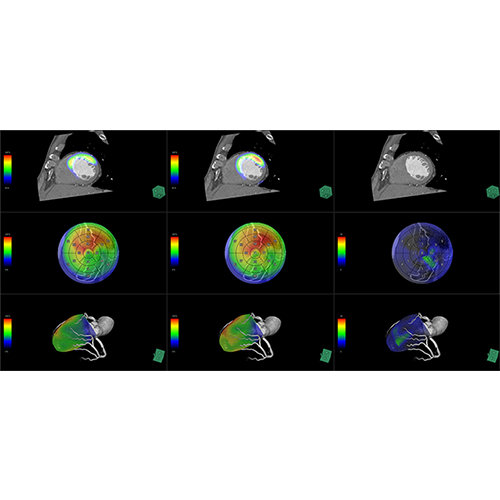

View X-Ray CT & MRI Scans Fast and Easily

Designed for surgeons, Pro Surgical 3D makes it easy to view patient scans quickly. Pro Surgical 3D facilitates the optimal 3D treatment and assessment workflows based on X-ray CT and MRI scans – and best of all, it’s FREE!

High-quality and fast 3D reconstruction and 3D rendering

Performs 3D reconstruction and volume rendering.

Multi-planar slicing.

Oblique slicing.